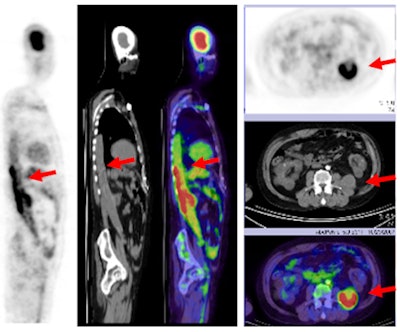

![]() |

| With the addition of FDG-PET, physicians discovered a graft infection in a 50-year-old male with kidney failure and fever of unknown origin, with high FDG uptake illustrating the malady. |